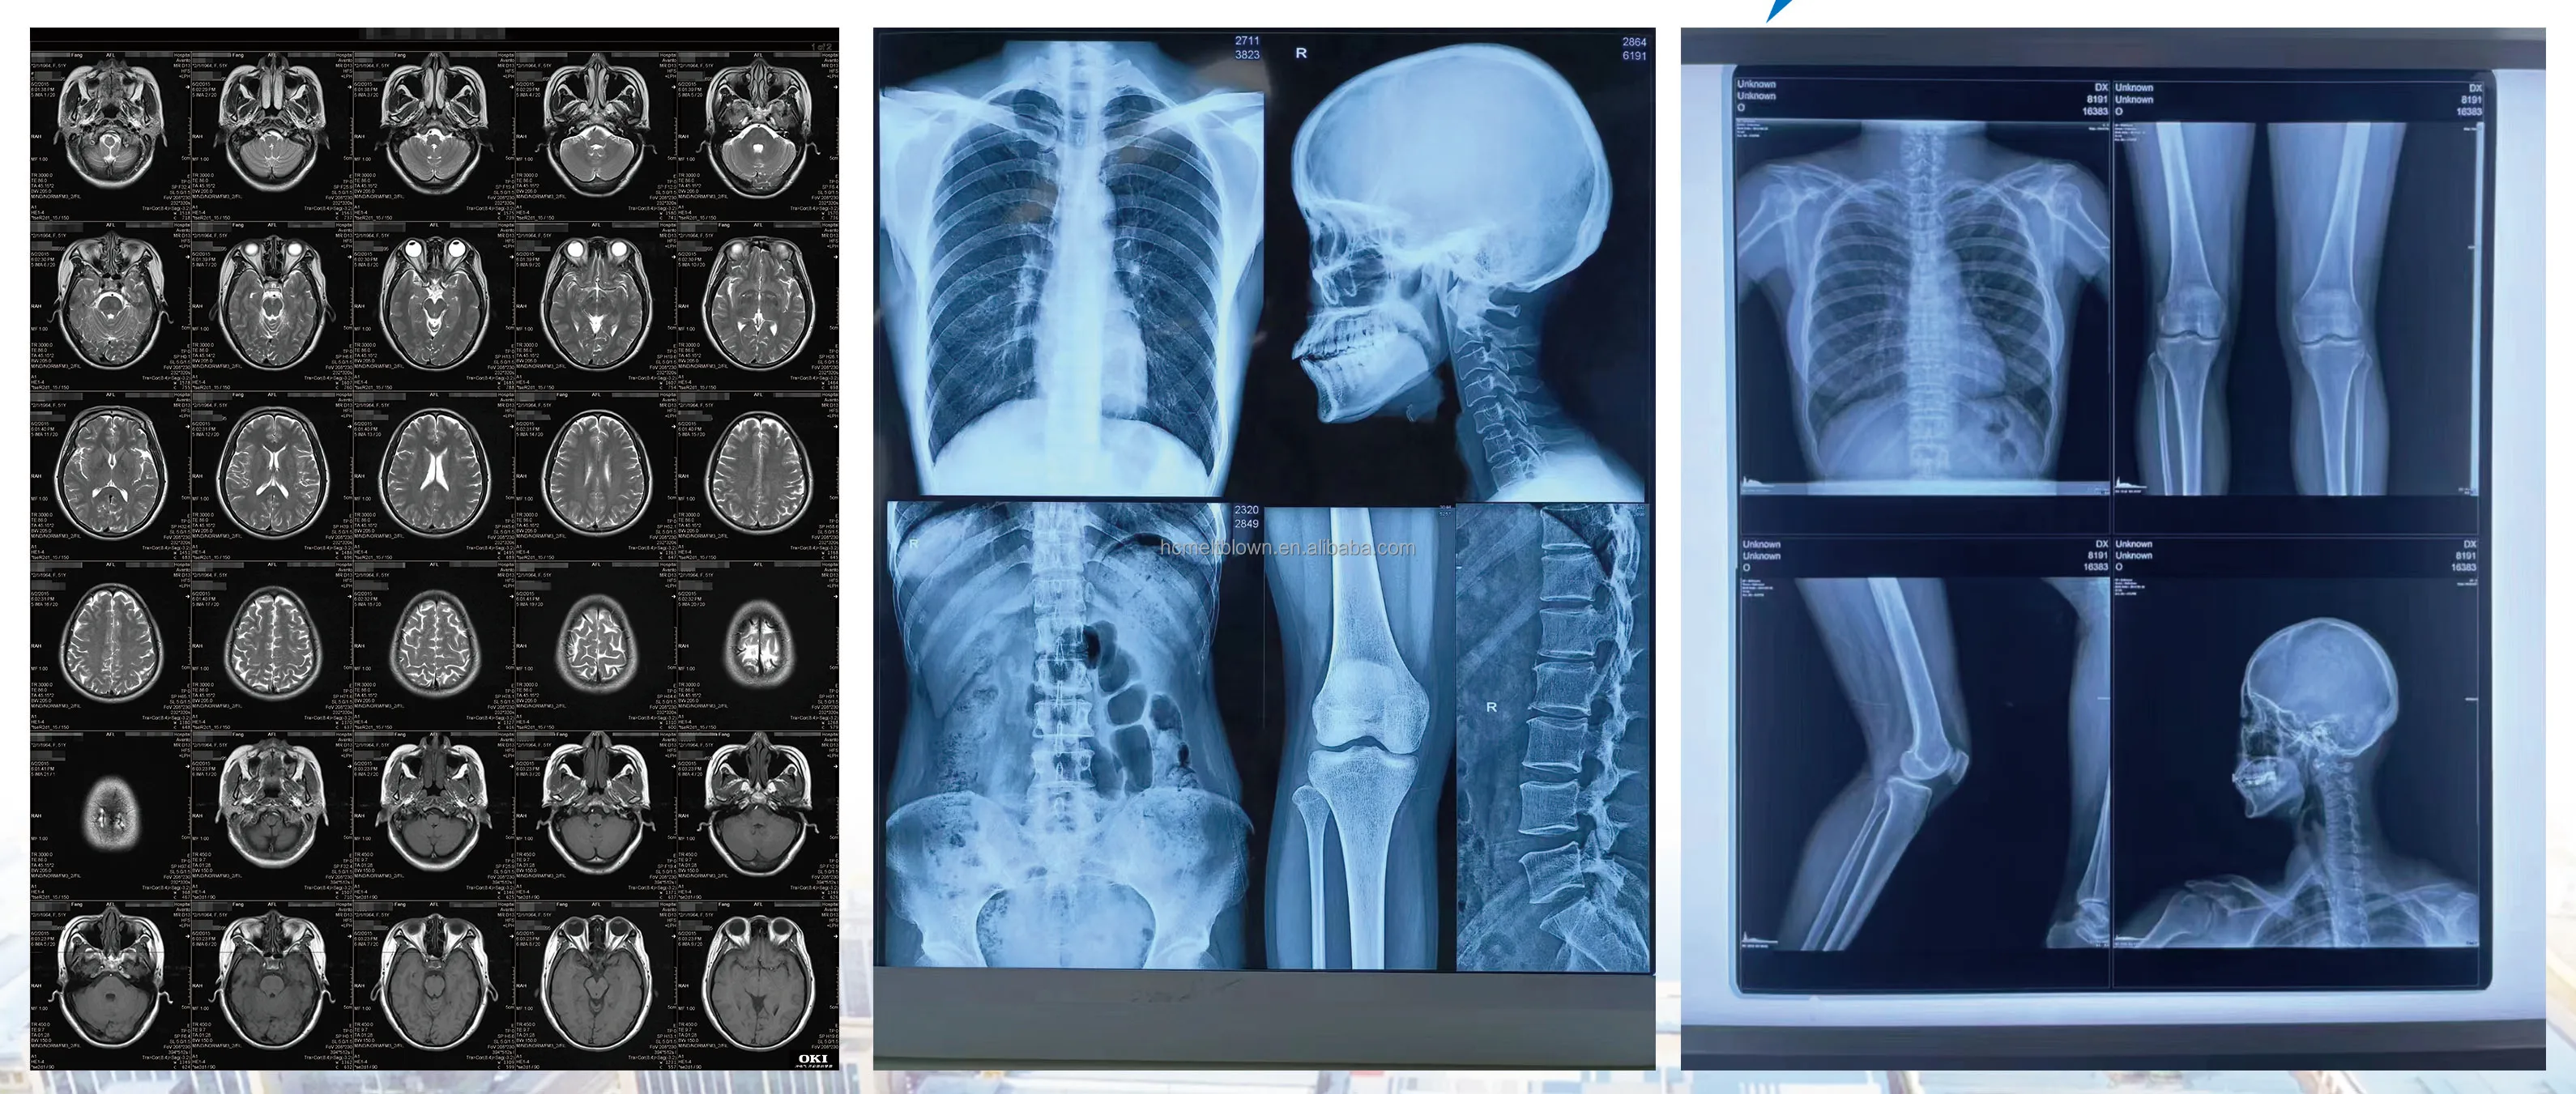

This film is cut by blue majorrols, coated with thermal imaging layer and thermal proctection layer, and doesn’t contain light-sensitive silver halide.

All of medical images stored digitally after computer processing can be reproduced by this film without any environmental pollution.

It is also suitable for printing and output of medical digital images such as CR, DR, CT, MRI etc. It can be used for printers of Agfa or other dry imaging equipments directly.

Detailed Images